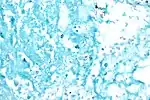

M. tuberculosis (stained red) in sputum

Purposediagnosed by finding Mycobacterium tuberculosis

Tuberculosis is diagnosed by finding Mycobacterium tuberculosis bacteria in a clinical specimen taken from the patient. While other investigations may strongly suggest tuberculosis as the diagnosis, they cannot confirm it.